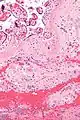

| Micrograph of a chronic deciduitis, showing the characteristic plasma cells. H&E stain. | |

Chronic deciduitis is a type of long-lasting inflammation that arises in pregnancy and affects the endometrial stromal tissue (decidua).

It is associated with preterm labour.[1] The diagnosis rests primarily on the presence of plasma cells.[2]